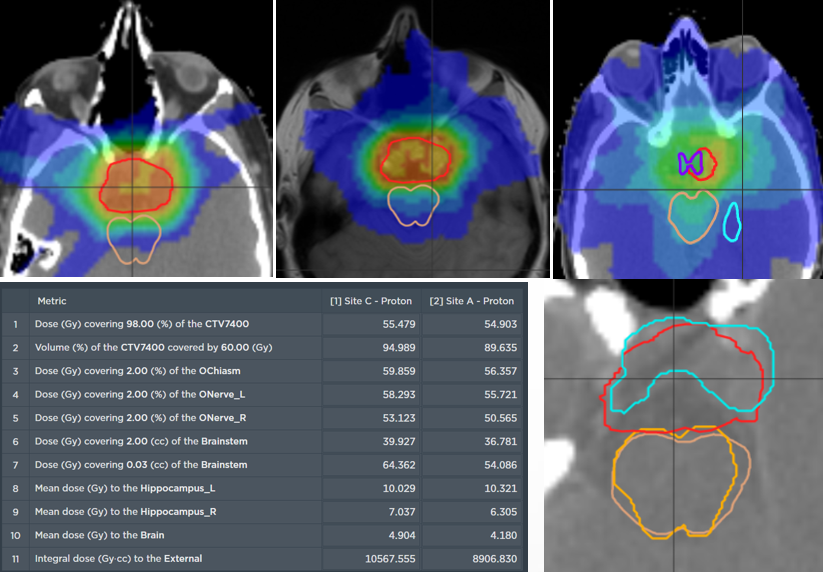

The comparative planning workshop featured an extremely complex case. The four participating centres each created comparative proton-photon treatment plans. The CTV was abutting critical organs at risk such as optic chiasm, optic nerves, brainstem and hippocampi. In addition to this, the requirement for a high prescription dose meant that significant optimization trade-offs were required.

The Australian Bragg Centre team utilized MonacoPT to generate the proton therapy treatment plan and used unique features including constrained optimization, dynamic spot placements and Linear Energy Transfer (LET) analysis. The robustness optimization display also allowed the team to view approximate doses during optimization, not having to navigate through multiple windows.

Dose view

LET view